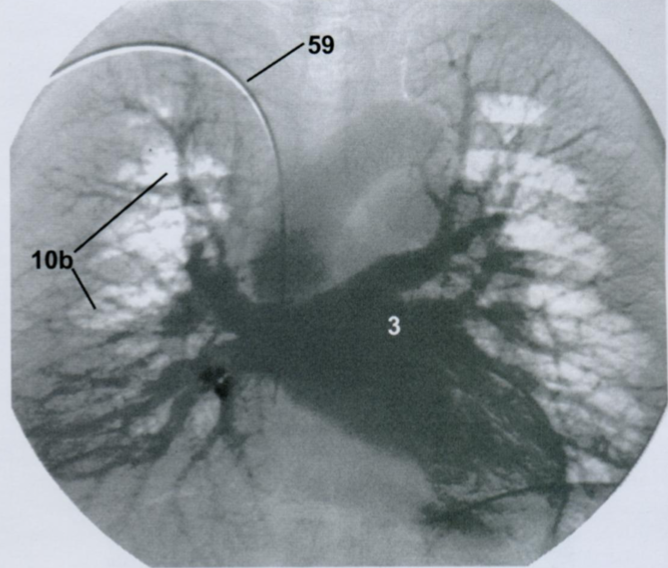

19

Q

Ангиографическая визуализация сосудов легких.

Какая фаза распространения контраста? Артериальная или венозная?

Назовите все пронумернованные структуры.

Ангиография выполняется с помощью введения контраста через катетер в полой вене, правом предсердии или артериях малого круга.

A

Венозная фаза. Норма.

3 - левое предсердие

10b - легочные вены

59 - катетер